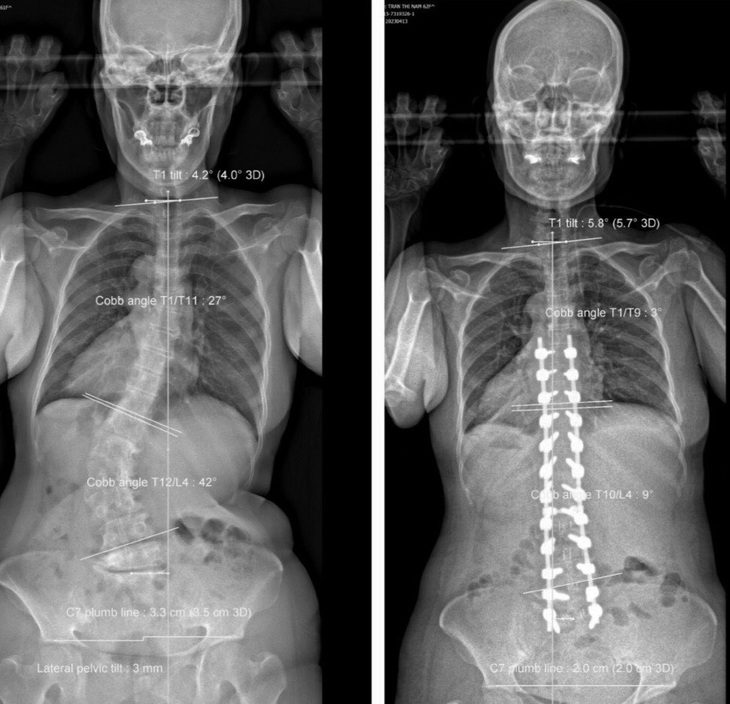

Hình ảnh trước và sau khi phẫu thuật của bệnh nhân 60 tuổi bị vẹo cột sống thắt lưng sang phải – Ảnh: Bác sĩ cung cấp

Kết quả chẩn đoán hình ảnh cho thấy bệnh nhân bi vẹo cột sống ngực – lưng 27 độ, vẹo cột sống thắt lưng 42 độ, thoái hóa cột sống ngực – lưng – thắt lưng, còng cột sống ngực – lưng, mất ưỡn cột sống thắt lưng.

Sau ca phẫu thuật kéo dài hơn 7 tiếng rưỡi đồng hồ, bệnh nhân cao thêm 8cm. Hiện bệnh nhân có dáng đi thẳng, người và phần đầu không còn đổ về trước khi đi hay đứng. Bệnh nhân cũng hết đau tê hoàn toàn chân phải, chân trái còn tê rất ít, sức cơ hoàn toàn bình phục.